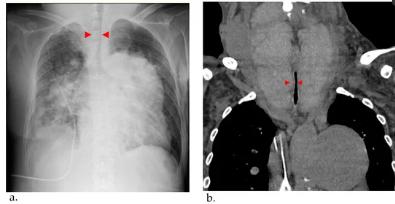

45岁时,依前列醇剂量增至32.5 ng/kg/min,但右心导管平均肺动脉压高至58 mmHg,控制不够。当时甲状腺肿大是轻微的(图1a)。因此医生进一步增加了依前列醇的剂量。经过16年的治疗,依前列醇维持在60-70 ng/kg/min,可以将其降至30 mmHg左右。虽然使用甲巯咪唑和左旋甲状腺素治疗Graves病控制了患者的甲状腺功能,但她的甲状腺肿大逐渐恶化(图1b)。54岁时,甲状腺检查显示TSH=3.33μIU/mL,游离T3=1.18 pg/mL,游离T4 = 3.06 pg/mL。然而,随着依前列醇的滴定,甲状腺肿进一步恶化(图1c)。

图一、甲状腺肿大的计算机断层成像过程。(a)45岁的时候。(b)52岁的时候。(c)54岁的时候。甲状腺逐渐增大

56岁时,患者因呼吸困难恶化被当地医院收治。然而,观察到心源性休克和呼吸衰竭伴高碳酸血症,第二天被转院。入院时,患者的生命体征为血压97/62 mmHg,脉搏117 bpm,通过面罩以10 L/min的速度吸氧,血氧饱和度88%。此时依前列醇的剂量为62.8 ng/kg/min。经检查,听诊发现心脏舒张期有肺动脉反流杂音,心脏第二心音的肺成分加重,肺部有粗裂音,颈部有喘鸣音。胸部x光显示双侧肺充血和气道狭窄(图3a)。胸部电脑断层扫描也显示她的巨大甲状腺肿导致气道狭窄(图3b)。

图3、(a)胸部X射线检测到肺充血、心影增大和气道狭窄(红色箭头)。(b)CT观察到甲状腺肿大。甲状腺肿引起的气管压迫和狭窄(红色箭头)